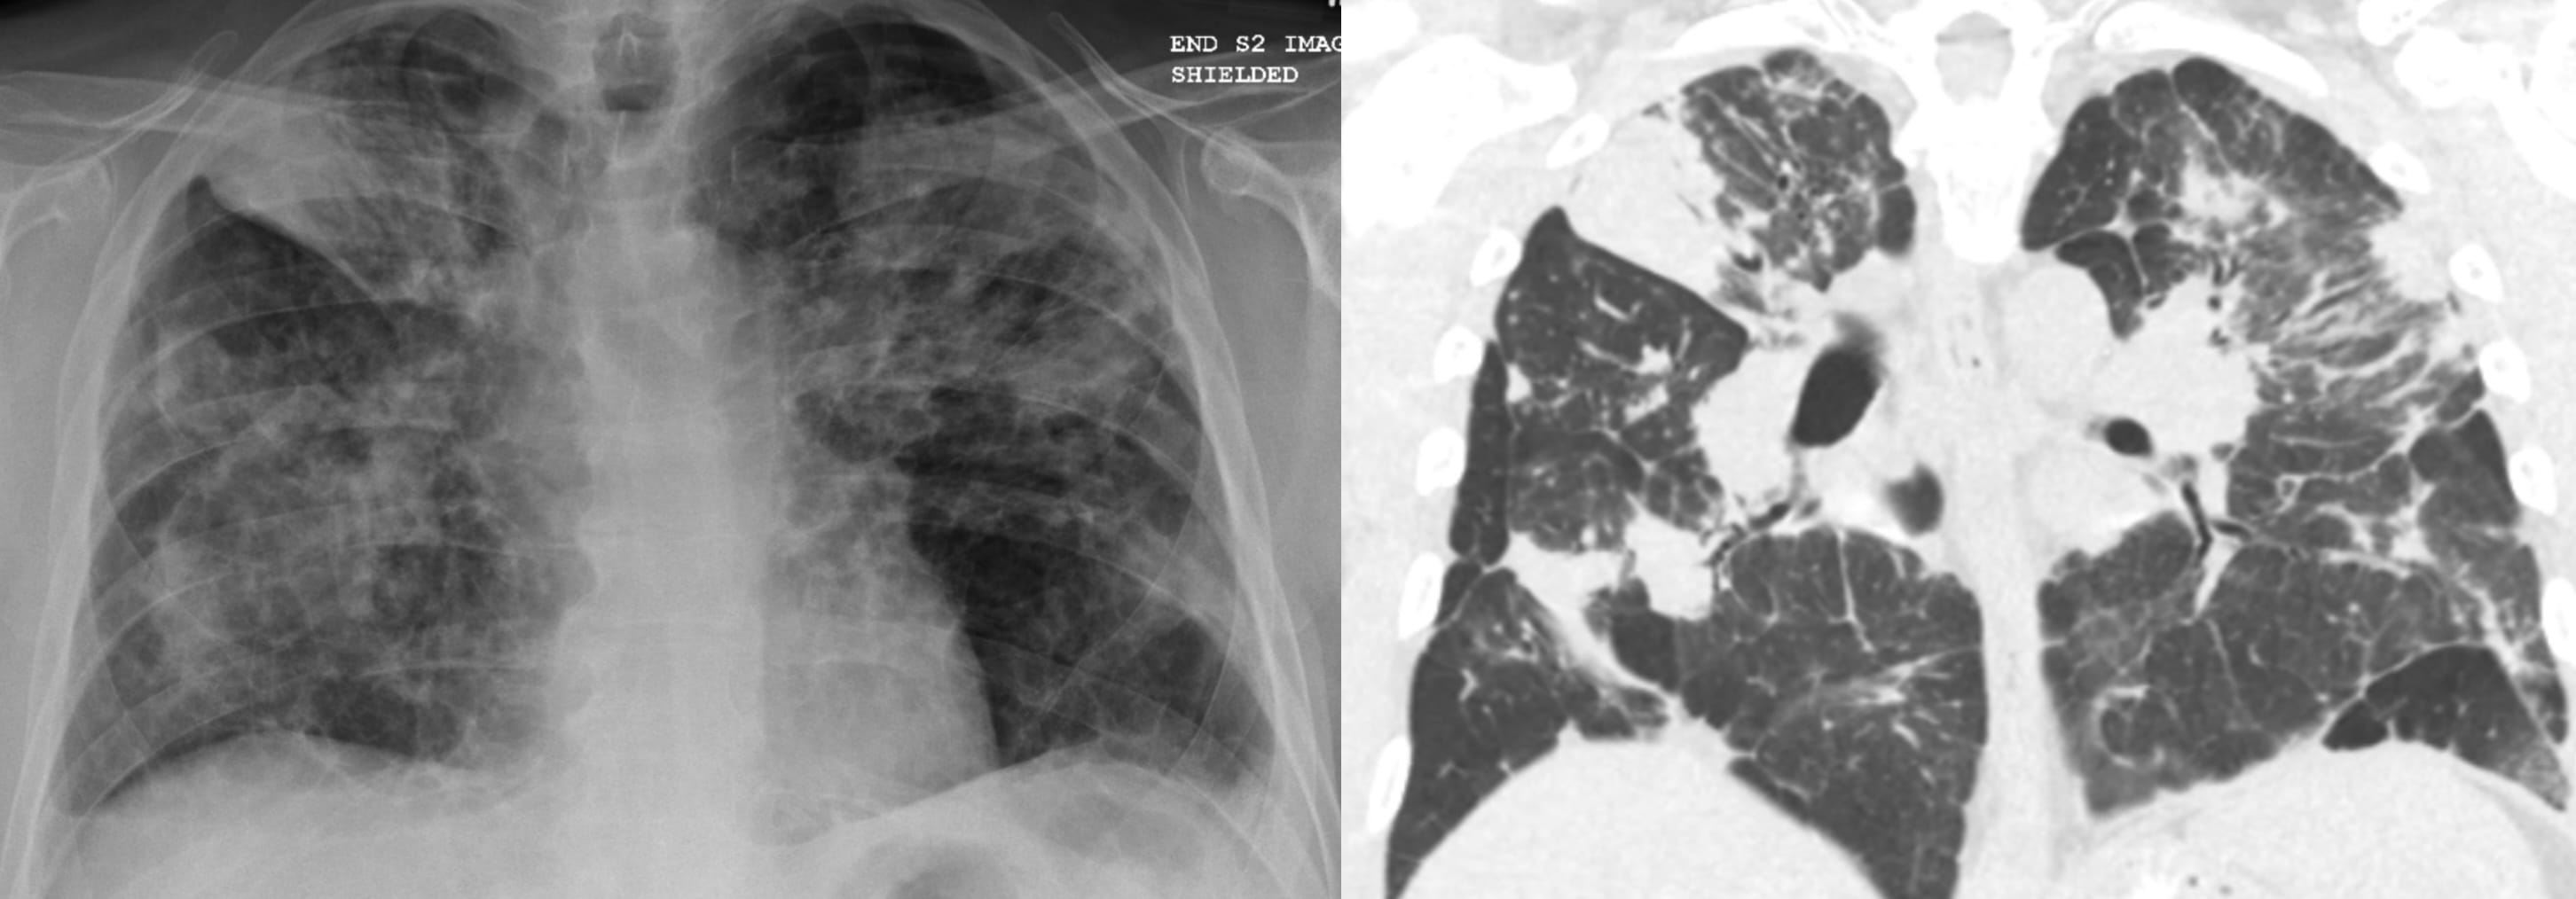

- Usual Interstitial Pneumonia